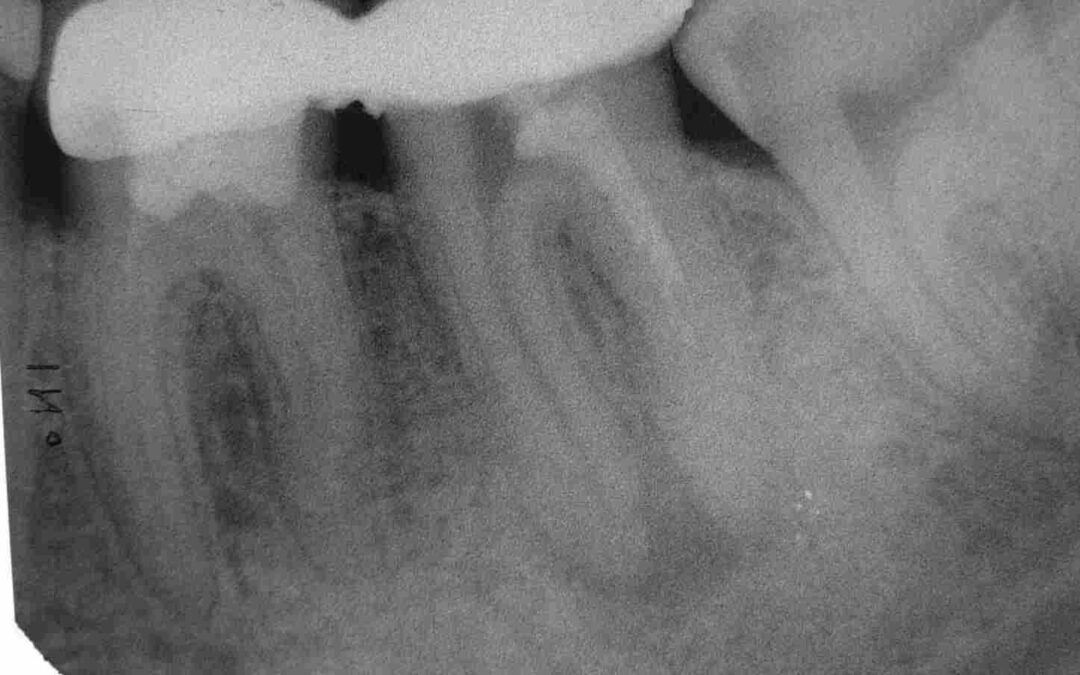

….und man ist ja auch nicht jeden Tag gleich gut drauf und in der Folge gleich leistungsfähig. Keine Ahnung, was dieser bulgarische Patient in seinen Wurzelkanälen hatte. Russisch-Rot war es nicht. Die Revision war in jedem Fall ausgesprochen mühsam.

Das war es dann aber noch lange nicht. Es lief weiter nach dem Motto: „Erst hatten wir kein Glück, und dann kam auch noch Pech dazu“. Wenn einmal der Wurm drin ist….. Letztlich kam es zur Hemisektion von 36.

Shit happens, und der, der frei von Misserfolgen ist, werfe den ersten Stein. Wichtig ist, dass man solche Komplikationen in den Griff bekommt, und trotzdem noch eine anständige Arbeit eingliedert.